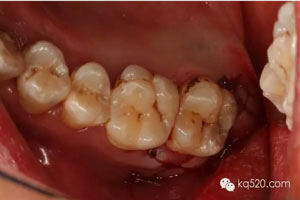

患者、曹xx、男、31歲。主訴:左側(cè)上后牙牙齦腫痛不適。有異味數(shù)月。專(zhuān)科檢查:28未萌出,可探及牙冠,捫診,有大量膿性分泌物溢出。x線片檢查:28遠(yuǎn)中水平阻生,牙根靠近27牙根的根方。診斷:28遠(yuǎn)中高位水平阻生伴冠周炎。治療計(jì)劃:建議拔除28.患者同意手術(shù)方案,簽知情同意書(shū)。

圖1.術(shù)前口內(nèi)像:上頜結(jié)節(jié)后份有一溢膿的瘺道,看不到28。

圖2.根尖片檢查:28遠(yuǎn)中水平阻生,看不清28牙根與上頜竇的關(guān)系,建議拍全景片。